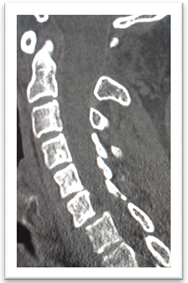

Female patients 25 years old was felled from height with modified Frankel’s grade D and DFI stage 2. Closed skull traction was failed. Posterior cervical approach, unlocking of the facet, bone fusion and lateral mass fixation with rods and screws (Figure 2).

Figure 2. Showing case 2 presentation. (a) Pre-operative CT (b) pre-operative CT with bone window (c) post-operative plain X-ray lateral mass rode and screws fixation and fusion.